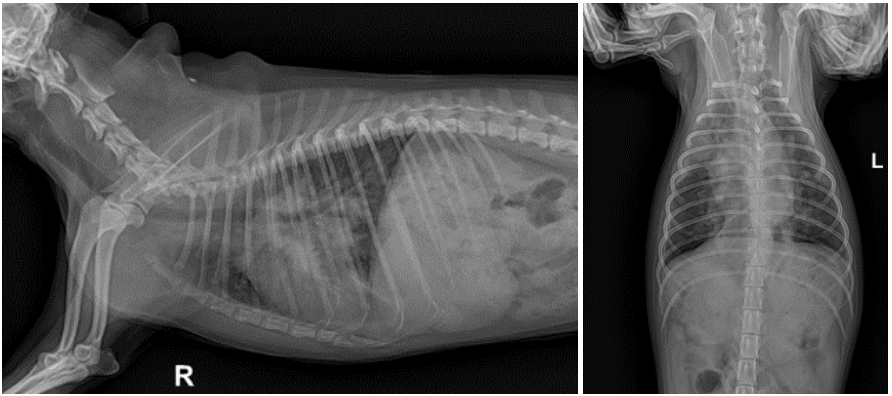

흉부방사선 상에서 폐전엽에 걸친 침윤이 있었으며 복배상에서는 결절로 의심되는 부분도 확인되었습니다. ▼

기침 호흡곤란 증상도 매우 좋아졌습니다. (방사선은 치료 후 3일 경과 사진) ▼